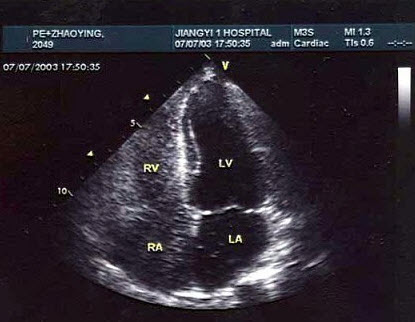

264、单项选择题 关于心尖四腔切面以下哪项不正确()

A.探头置心尖呈水平扫查

B.图像近场为心尖,远场为心底

C.十字交叉位于心脏中间处

D.左心室在右侧,右心室在左侧

E.可清晰显示左右房室瓣的活动

265、单项选择题